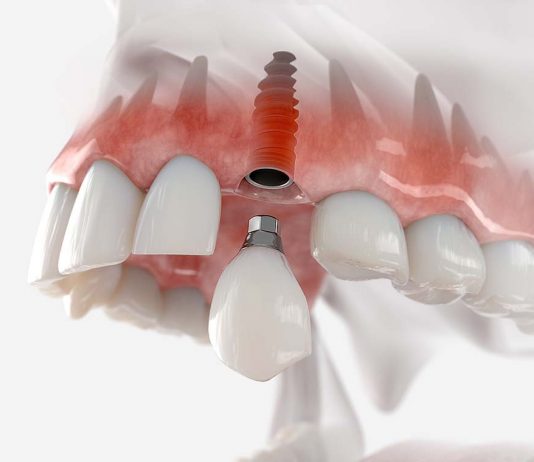

Имплантация зубов – это современная стоматологическая операция, представляющая собой установку искусственного корня на место отсутствующего зуба. С помощью имплантатов проводят протезирование зубов, которое позволяет восстановить функции и эстетику улыбки.

Клиника «SmileClinic» проводит ИМПЛАНТАЦИЮ ЗУБОВ тут https://smilespb.ru/uslugi/implantatsia_zubov_pod_kluch/ с применением самых передовых технологий. Также это оборудование позволяет сделать их максимально комфортными для...